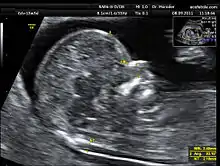

Nakkefoldsscanning er en ultralydsundersøgelse, hvor man måler størrelsen på fosterets nakkefold. Scanningen er non-invasiv og regnes for helt ufarlig.

nakkefold